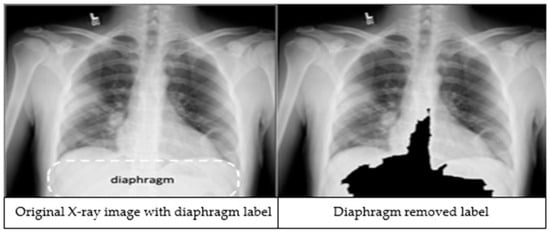

The third preprocessing technique focuses on improving classification accuracy by removing the diaphragm region (see Figure 2) from the X-ray images. The process begins by identifying the maximum and minimum pixel intensities, namely imax and imin respectively. A binary threshold t = imin + 0.9 * (imax − imin) is then applied to convert the image into a binary segmented image. Afterwards, a morphological closing is applied on the binary segmented image to make it a refined mask. Finally, a bitwise operation is performed using the mask image to remove the diaphragm area from the original image, resulting in an image which is called Id.

Figure 2.

An X-ray image showing the diaphragm region of the image within the dashed lines (left). The image after applying the diaphragm removal technique (right).

We applied image preprocessing techniques to automatically detect and remove the diaphragm region from chest X-ray images. Comparative analysis revealed that excluding the diaphragm significantly improved classification accuracy, increasing from 92.69% to 97.29%. While deep learning models are typically capable of learning relevant features without explicit segmentation, our findings demonstrate that removing irrelevant regions through preprocessing can enhance both the performance and robustness of the models.